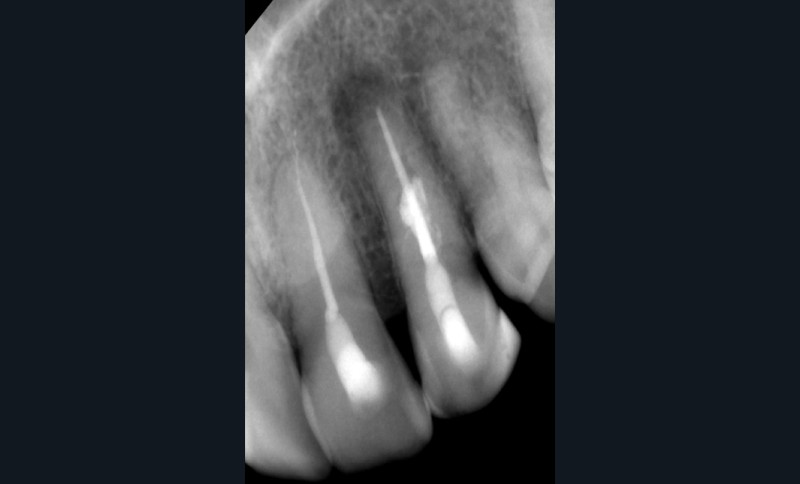

L’utilisation du scanner, et maintenant du CBCT, bouleverse l’idée très radiographique que nous avions du système canalaire.

En effet, la culture endodontique, fondée sur les critères radiographiques, a fait oublier les études de Hess et Zurcher (1925) qui mettent en évidence la complexité du système endo-canalaire [1]. Ce système présente une cavité principale (par exemple, le canal principal) ainsi que des canaux accessoires/latéraux. 25 % de ces microcanaux peuvent être interconnectés les uns aux autres, avec une densité plus importante de ramifications dans la région apicale du canal principal [2].

Rebondissant sur l’imagerie 3D et la mise en évidence des anatomies canalaires complexes, Peters, en 2001, décrit l’insuffisance instrumentale dans le traitement endodontique, et montre que 35 % des surfaces sont intactes après préparation canalaire correctement menée [18].

Endal, en 2011, montrait également, en utilisant le micro CT Scanner, l’insuffisance de nettoyage des isthmes inter-canalaires à nos techniques conventionnelles [19]. L’utilisation du laser Er:YAG devenait alors incontournable dans le nettoyage de ces isthmes et des zones non instrumentées (fig. 2 et 3).